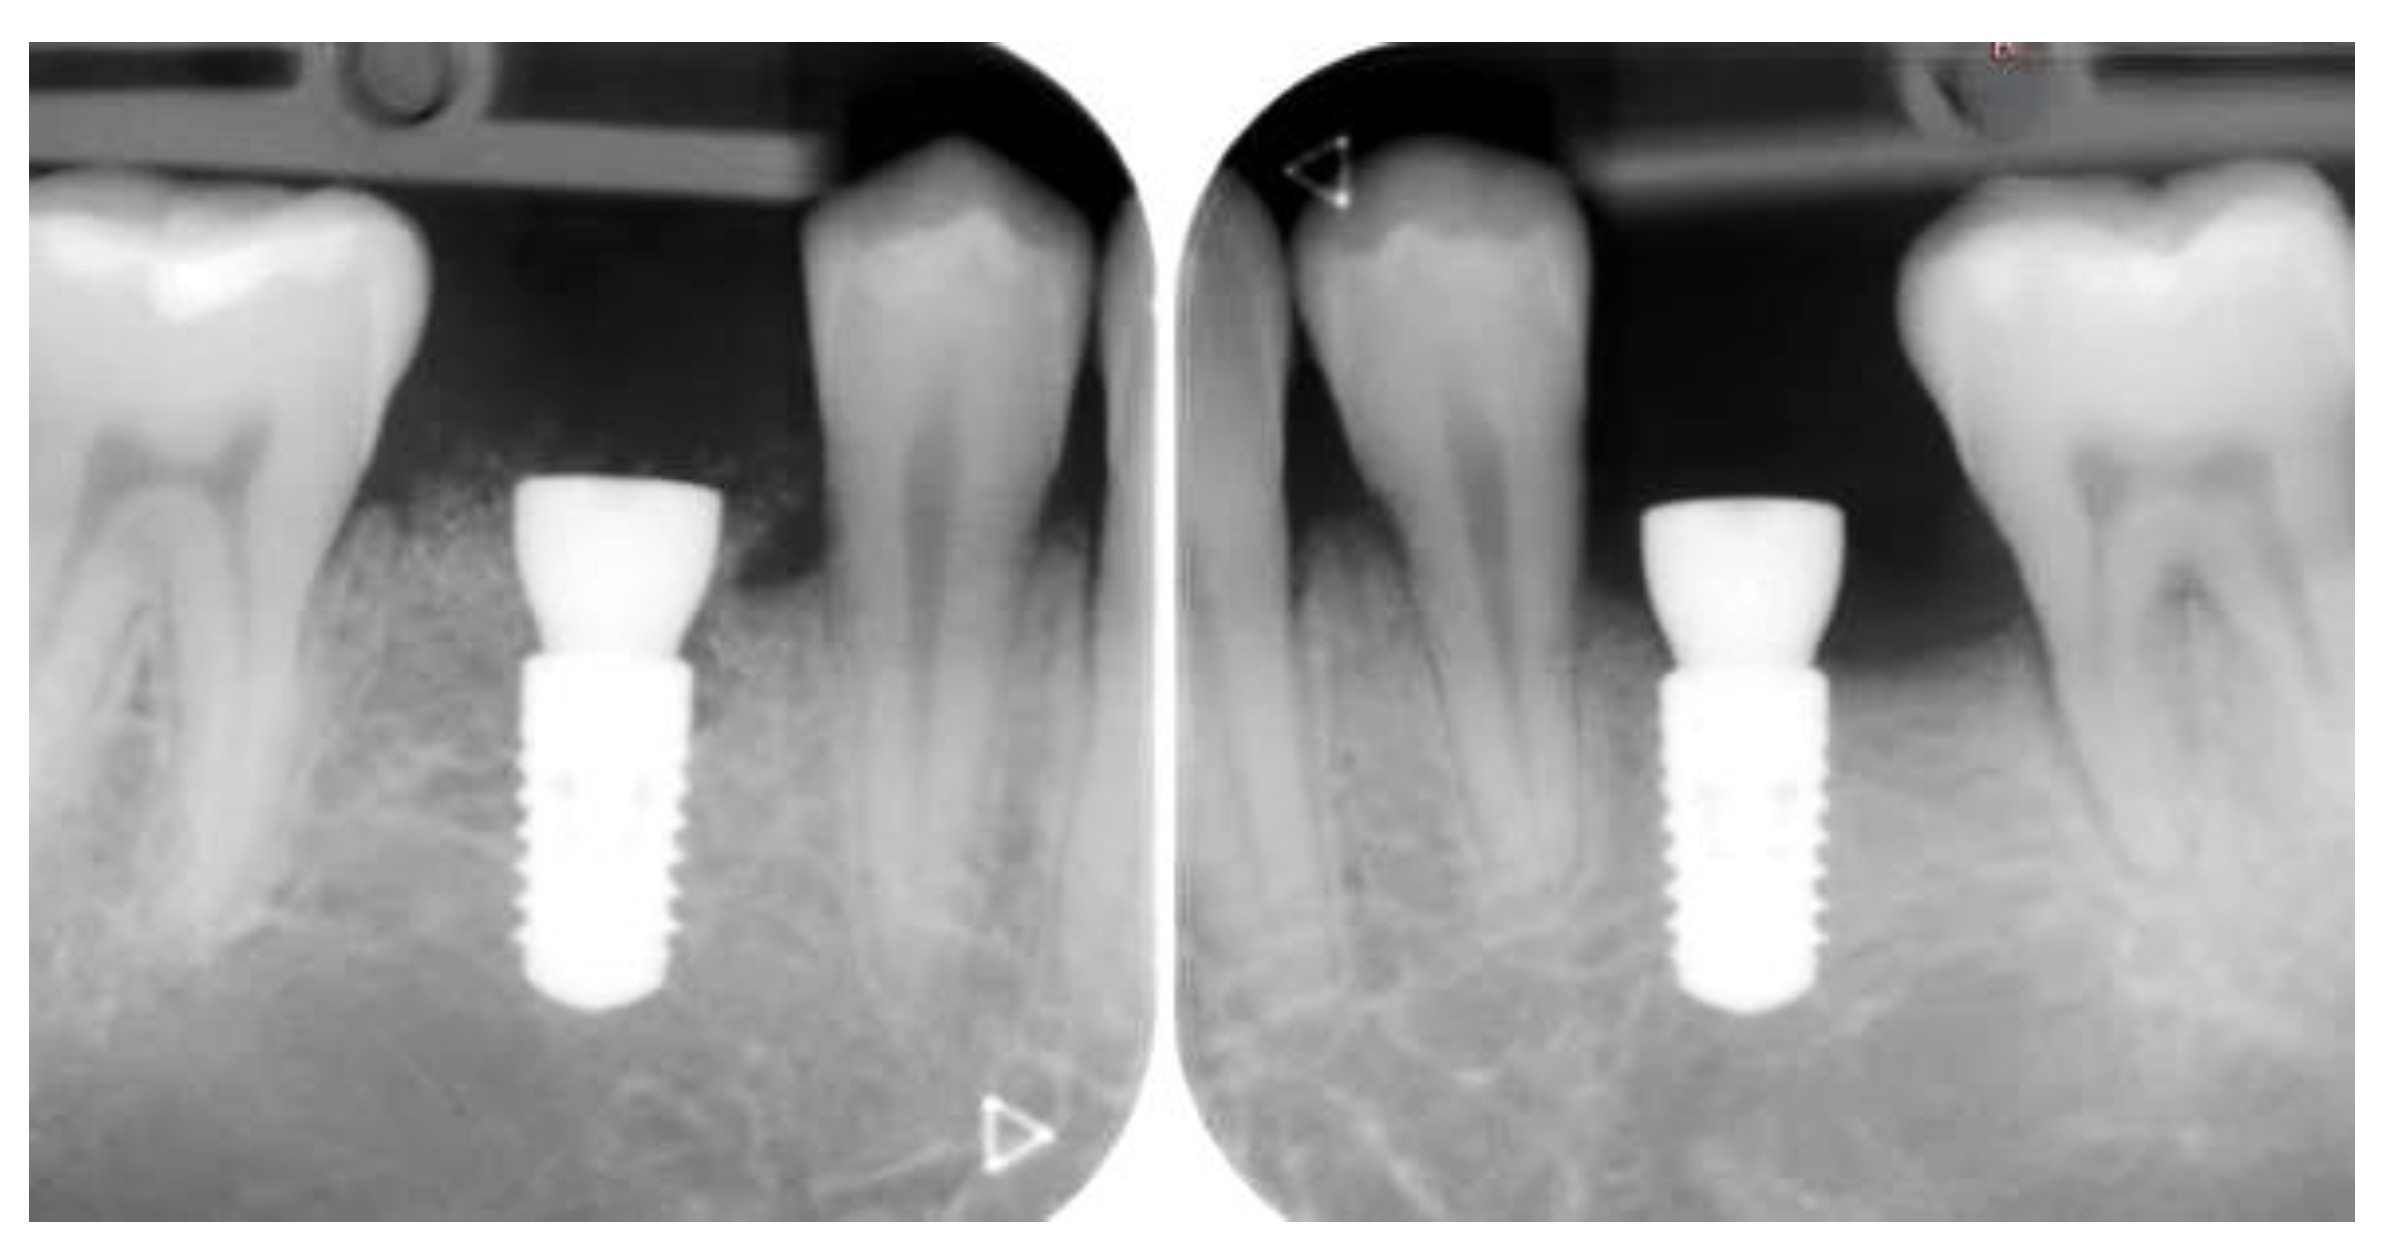

2.4.1. Radiographic Measurements

3.2. Marginal Bone Level Outcomes